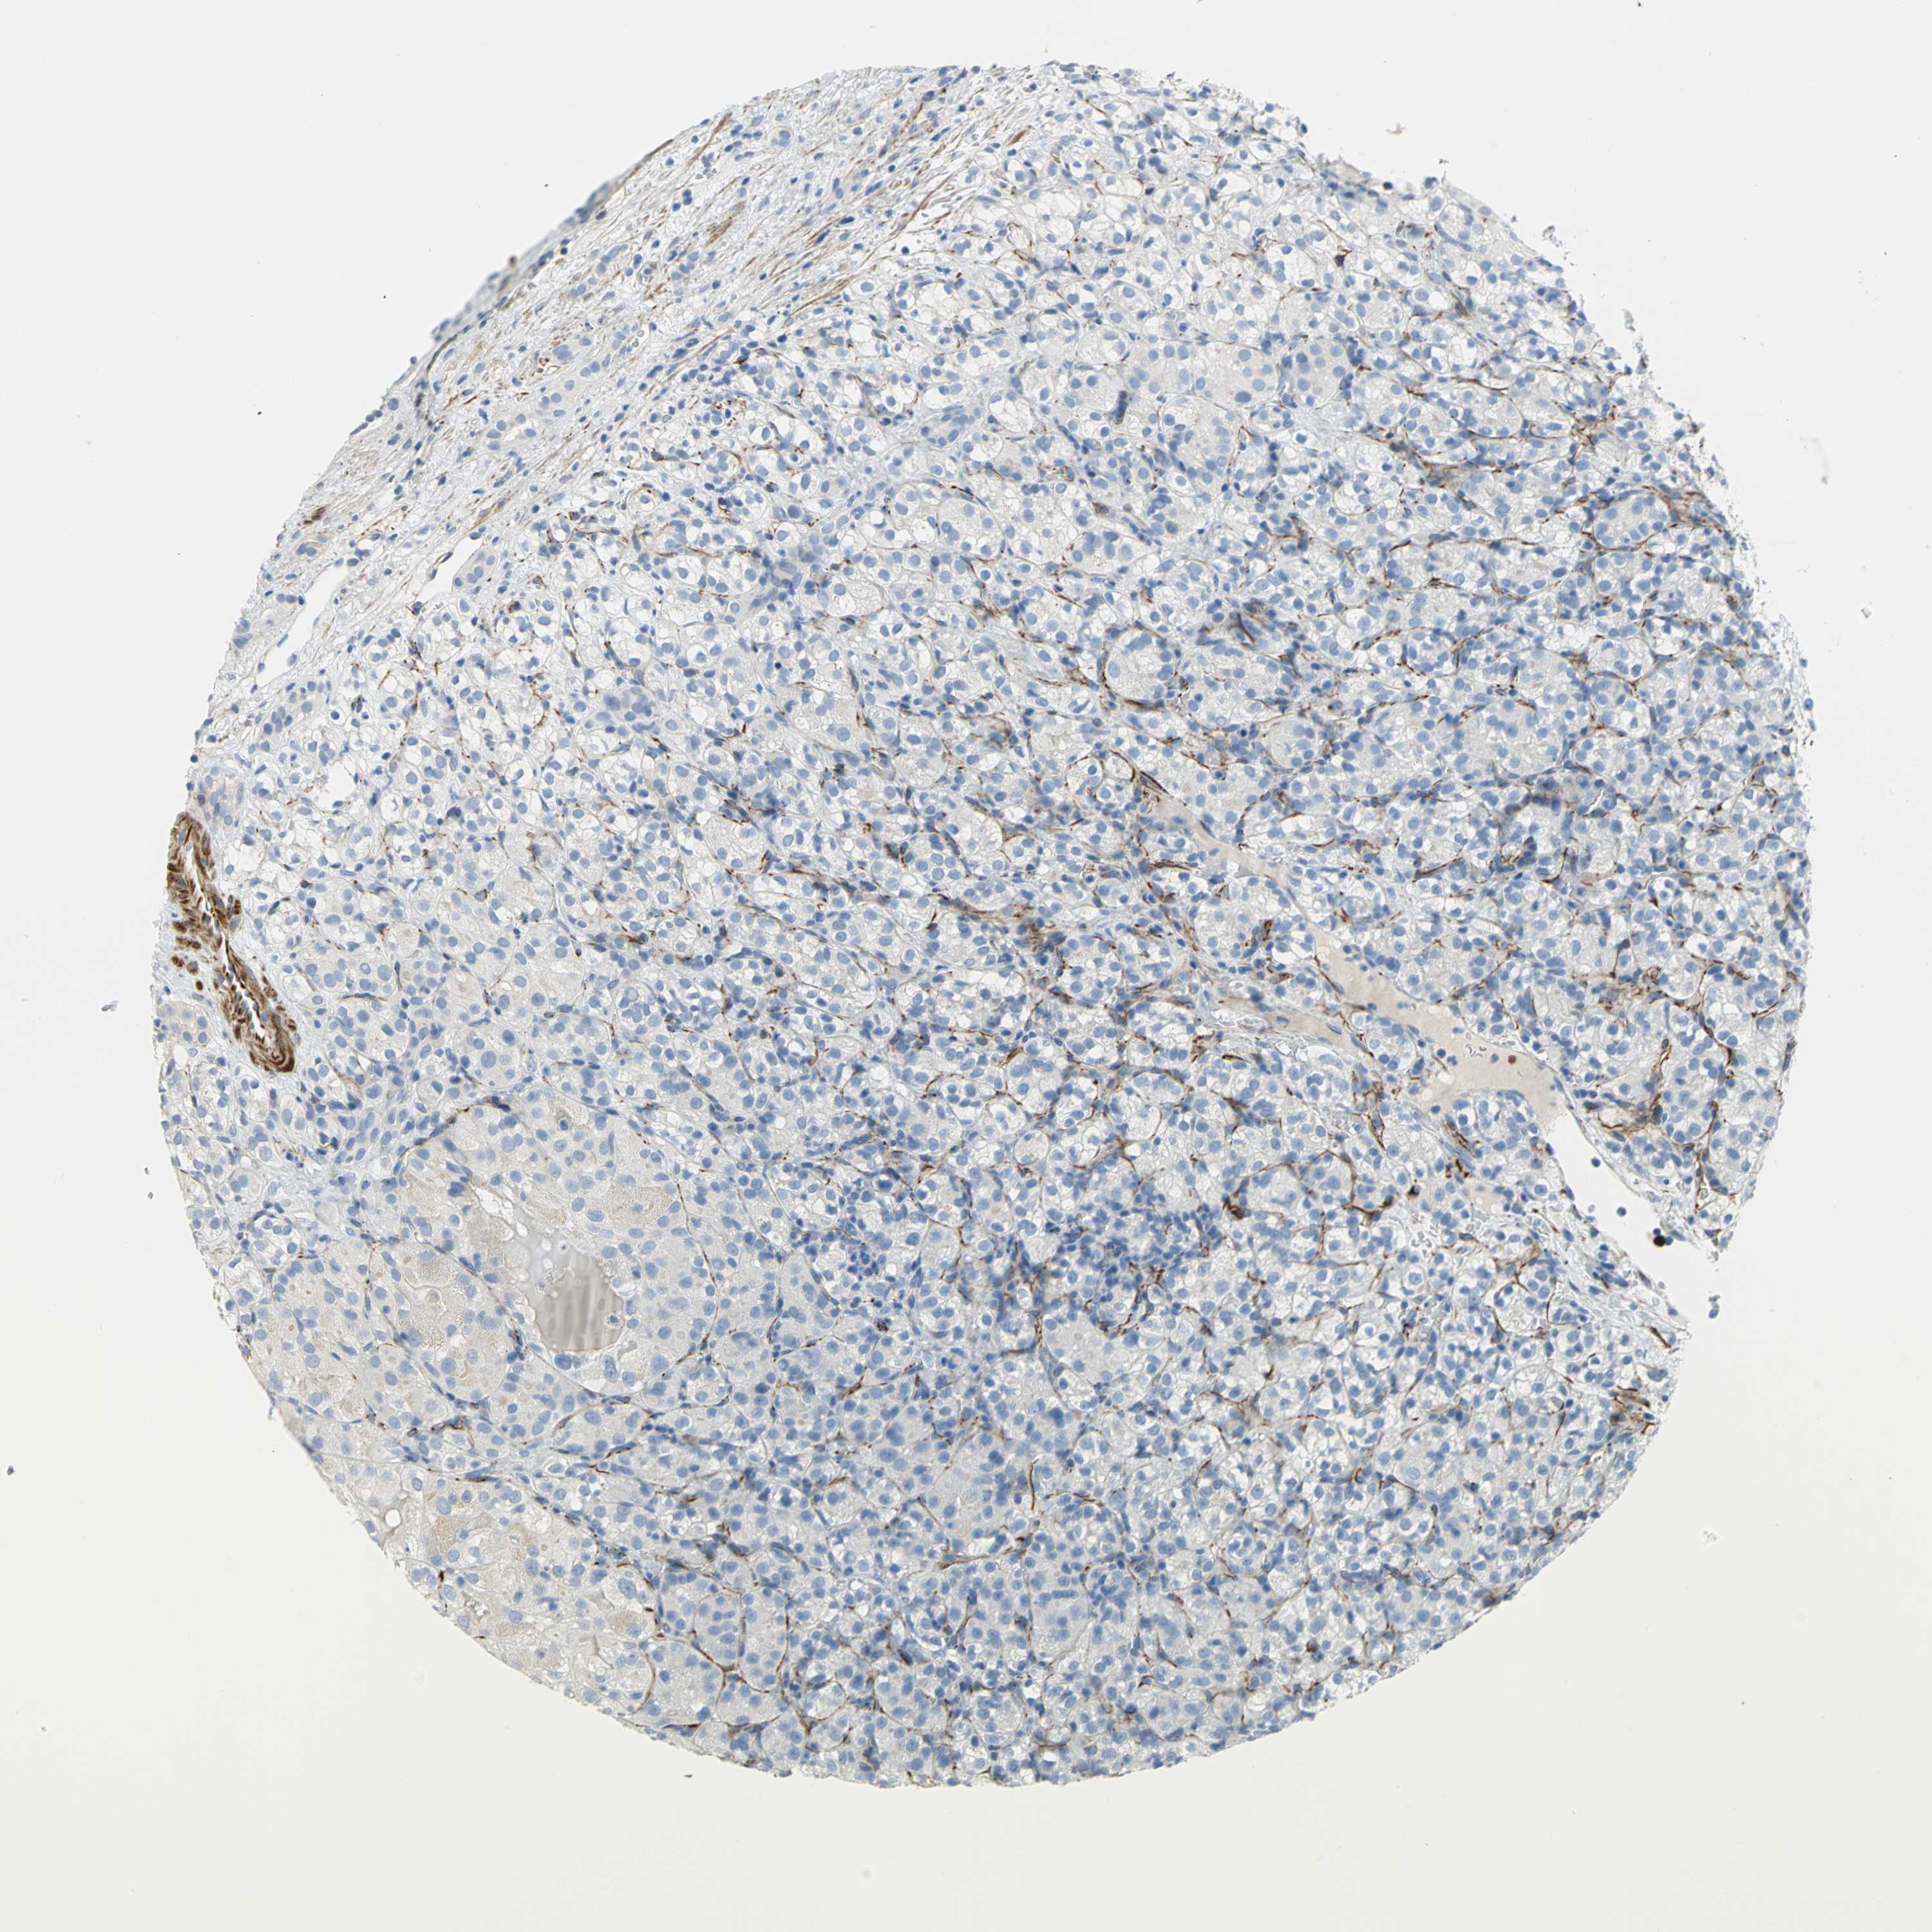

KIDNEY RENAL CLEAR CELL CARCINOMA (VALIDATION) - Interactive survival scatter ploti

The Survival Scatter plot shows the clinical status (i.e. dead or alive) for all individuals in the patient cohort, based on the same data that underlies the corresponding Kaplan-Meier plots. Patients that are alive at last time for follow-up are shown in blue and patients who have died during the study are shown in red.

The x-axis shows the expression levels (FPKM) of the investigated gene in the tumor tissue at the time of diagnosis. The y-axis shows the follow-up time after diagnosis (years). Both axes are complimented with kernel density curves demonstrating the data density over the axes. The top density plot shows the expression levels (FPKM) distribution among dead (red) and alive patients (blue). The right density plot shows the data density of the survived years of dead patients with high and low expression levels respectively, stratified using the cutoff indicated by the vertical dashed line through the Survival Scatter plot. This cutoff is automatically defined based on the FPKM cutoff that minimizes the p-score. The cutoff can be changed by dragging the vertical line or by entering a cutoff value in the square labeled "Current cut-off".

Under the Survival Scatter plot the p-score landscape (black curve; left axis) is shown together with dead median separation (red curve; right axis). Dead median separation is the difference in median mRNA expression between patients who have died with high and low expression, respectively. It is calculated as follows: median FPKM expression of dead patients with high expression - median FPKM expression of dead patients with low expression. This is intended to aid the user in visually exploring custom cutoffs and the associated p-scores and dead median separation.

Individual patient data is displayed and can be filtered by clicking on one or more of the category buttons on the top of the page. Categories describing expression level and patient information include: high, low, alive, dead, female, male and tumor stages. The scale of the x-axis can be toggled between linear and log-scale by clicking on the "x log" button. Mouse-over function shows TCGA ID, patient information and mRNA expression (FPKM) for each patient.

& Survival analysisi

Kaplan-Meier plots summarize results from analysis of correlation between mRNA expression level and patient survival. Patients were divided based on level of expression into one of the two groups "low" (under cut off) or "high" (over cut off). X-axis shows time for survival (years) and y-axis shows the probability of survival, where 1.0 corresponds to 100 percent.

ALOX15 is not prognostic in Kidney Renal Clear Cell Carcinoma (validation)

TCGA RNA samplesi

RNA-seq data is reported as average FPKM (number Fragments Per Kilobase of exon per Million reads), generated by the The Cancer Genome Atlas (TCGA) .

Normal distribution across the dataset is visualized with box plots, shown as median and 25th and 75th percentiles. Points are displayed as outliers if they are above or below 1.5 times the interquartile range. FPKM values of the individual samples are presented next to the box plot.

Average pTPM 0.0

Number of samples 100